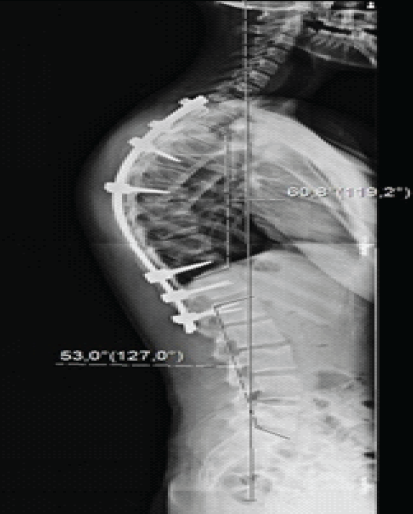

Given the severity and progressive nature of the deformity, posterior spinal instrumentation and fusion were performed. Pedicle screws were inserted at T5, T7, T11, T12, and L1; transverse process hooks were applied at T2 and T3 levels; and Smith-Petersen osteotomies were carried out from T6 to T10. Deformity correction was achieved using the cantilever technique, followed by posterolateral fusion with autologous bone graft. Intraoperative neurophysiological monitoring remained stable throughout the procedure. Post-operative imaging confirmed satisfactory correction, with a reduction of the thoracic Cobb angle to 60° (Fig. 2).

Figure 2: Post-operative full-length spine lateral view radiographs showing a Cobb angle of 60° and neutral sagittal vertical axis.